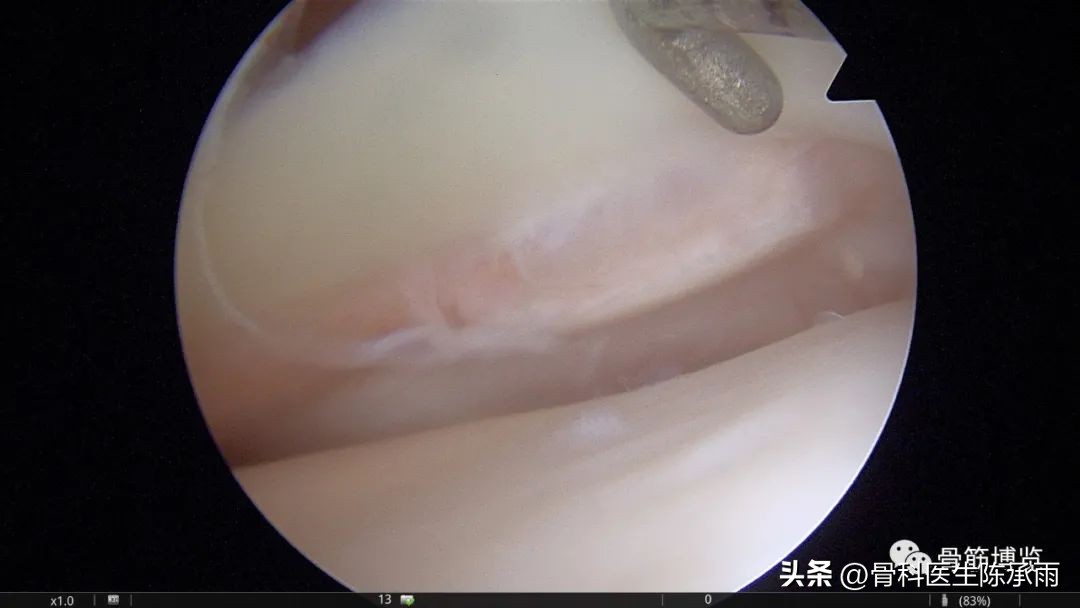

手术继续,患者术前表现为内侧间隙压痛明显,探查内侧半月板无异常,没有任何损伤。最后探查外侧半月板后角下表面可见一处活瓣样撕裂。

新鲜化撕裂创面,活瓣活动性较大,及易脱出,探之稍硬。

将“活瓣”翻转见光滑关节面,探之较硬,原来是个骨性游离体。

这种情况还是很少见的,应该是外伤后造成关节面骨块脱落,嵌于半月板后角及胫骨平台间的间隙内,骨块粗糙面与关节面长期摩擦后粘连包裹,并和半月板成一体,被误认为半月板撕裂,还好没有直接缝合。